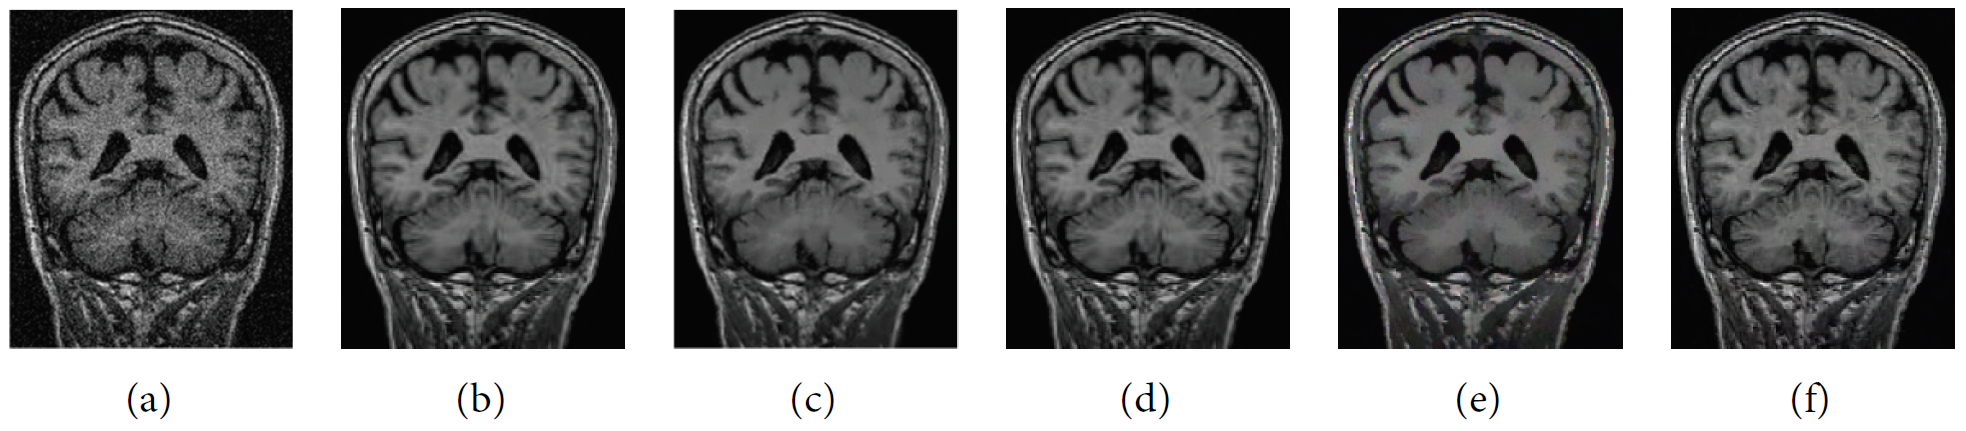

Our method and LG-NLM were performed in MATLAB 2015b, and the source programs of NLM, LRNLM, and BM3D were obtained in the author’s website. Fig. 1 shows the results of different denoising methods on noise MRI images with the same parameters.

Fig. 1.

Experiment results of MRI images. (a) Noise MRI slice. With test denoising methods, (b) NLM, (c) LG-NIM, (d) BM3D, (e) LR-NLM, and (f) our proposed method.

Fig. 1(b)–1(f) show that our method obtains the best PSNR in dB, compared with other methods. Fig. 2(b) presents the detail of the image in Fig. 2(a) after zooming. Fig. 2(c)–2(f) exhibit the denoising results of different methods, including LG-NLM, BM3D, and LR-NLM. Our method can effectively obtain noise suppression, texture preservation, and clearer details than other methods. For example, recovered results of the lady’s headscarf are hardly possible to achieve due to texture details, as demonstrated in Fig. 2(d)– 2(f). Moreover, many artifacts are visible near the headscarf. The recovered results of LG-NLM and LRNLM methods are inclined to contain more blocking artifacts than those of other methods. Our method demonstrates clearer detail preservation and edge sharpness than the traditional NLM methods. The reason is that the proposed method with fuzzy metric has the best quality, and it can lower the artifacts by measuring the subtle changes in the image structure.